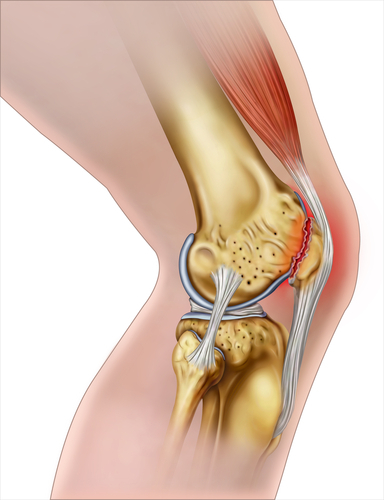

무릎 통증은 크게 내측, 외측, 전면, 후면으로 나눌 수 있습니다. 여기에서는 전면의 통증에 대해 알아보겠습니다.

무릎의 겉 구조물을 살펴보면

슬개골(Patella), 슬개건(Patella ligament), 대퇴사두근(Quadriceps femoris), 대퇴사두근건(Quadriceps tendon), 내측슬개지대(Medial retinaculum), 외측슬개지대(Lateral retinaculum)로 구성됩니다.

관절강 안으로 들어가면

내측반월판연골(Medial meniscus), 외측반월판연골(Lateral meniscus), 전십자인대(Anterior cruciate ligment), 반월판 연골과 경골을 연결해 주는 관상인대(Coronary ligment)가 있습니다.

그럼 통증 부위에 따라 원인을 살펴보도록 하겠습니다.

1번: 슬개골 연골 연화증(Patella chondromalacia), 관절염(Arthritis), 점액낭염(Bursitis), 슬개골골절(Patella fracture)

2번: 오스굿슐레터병(Osgood-Schlatter Disease)

3번: 대퇴사두근건염(Knee quadriceps tendinosis)

4번: 관상인대염좌(Coronary ligment sprain), 반월판연골손상(Meniscus injury)

5번: 슬개건염(Patellar tendinitis)

앞무릎 전체 통증: 대퇴신경 포착(Femoral nerve entrapment)